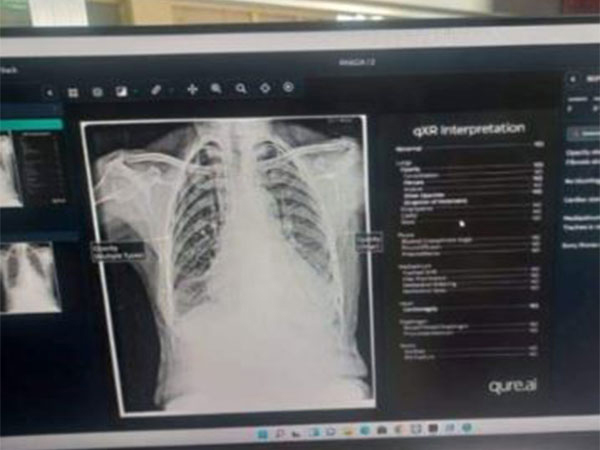

Under the guidance of the Directorate of Health Services Kashmir, the hospital has initiated a pilot project for Quick X-ray (Qxr), utilizing AI tools for more efficient diagnoses.

This innovative approach allows for the instant identification of abnormal areas in X-rays with an accuracy of over 90 per cent, greatly facilitating the final diagnosis process for radiologists.

The implementation of artificial intelligence at District Hospital Shopian brings numerous benefits to radiologists, streamlining their work processes. These advantages include more accurate classification of abnormalities, enhanced analysis capabilities, and faster delivery of results.